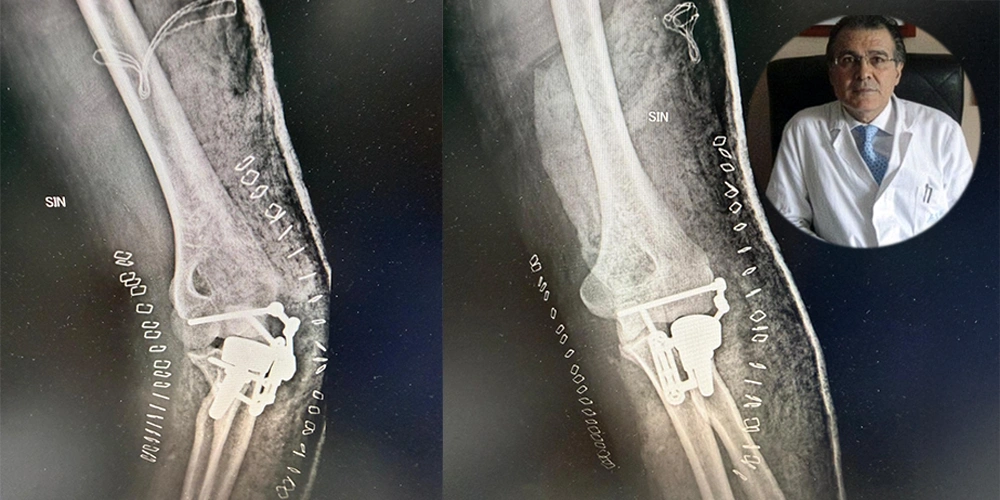

L’intervento, durato più di 4 ore, è stato eseguito con l’impiego di tecnologie di altissimo livello. Utilizzati uno stabilizzatore interno articolare e protesi capitellare di ultima generazione, con sistemi di fissaggio legamentosi mini-invasivi non metallici e con possibilità di consentire l’immediato ripristino della stabilità articolare. In sostanza la più precoce riabilitazione possibile. L’applicazione di queste tecniche, utilizzate nei più avanzati centri di riferimento internazionali, tra cui la Mayo Clinic (USA), confermano l’elevato standard tecnologico e professionale del Centro di Alta Complessità Ortopedica del Gruppo NefroCenter, guidato dal Professore Raffaele Russo, attivo presso la Casa di Salute Santa Lucia di San Giuseppe Vesuviano e la Clinica Villa dei Fiori di Mugnano.

Il Prof. Raffaele Russo, Professore Straordinario di Ortopedia e Traumatologia presso la Facoltà di Medicina e Chirurgia “Vincenzo Tiberio” di Campobasso, vanta un curriculum di assoluto rilievo: 19 anni di Primariato di Ortopedia e Traumatologia presso l’Ospedale dei Pellegrini di Napoli con Direzione del Dipartimento delle Emergenze, già presidente della Società italiana di Chirurgia della Spalla e del Gomito è riconosciuto come uno dei Padri fondatori della chirurgia della spalla e del gomito in Italia, con esperienza internazionale e certificata dalla Società Europea della Spalla e del Gomito come eccellenza europea.